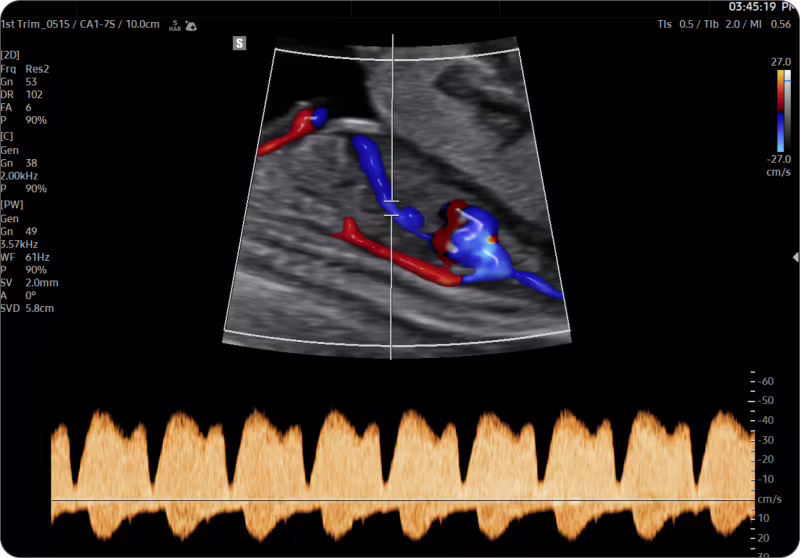

1.trimestrální screening včetně stanovení rizika preeklampsie dle FMF London (Fetal Medicine Foundation - London)